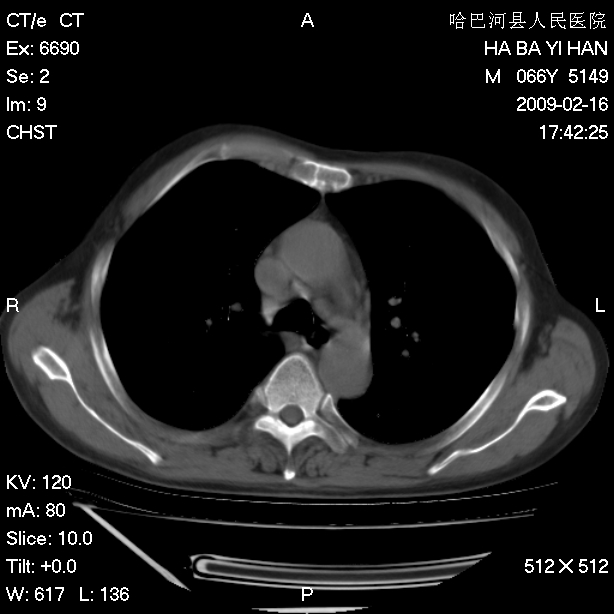

以下是引用huangxun4321在2009-2-16 20:18:00的发言:[br]部分病灶可见硬化边,部分可见骨质破坏消失,部分病灶内可见骨脊,说明病灶内既有良性病变,又有恶性病变,考虑骨巨细胞瘤恶变,未除骨纤恶变,畸形性骨炎少见,亦要考虑.

以下是引用731208在2009-2-16 20:31:00的发言:[br]考虑恶性胸膜间皮瘤并肋骨,脊柱转移。

以下是引用yijiansheng在2009-2-16 20:16:00的发言:[br]考虑恶性胸膜间皮瘤并肋骨,脊柱转移。

以下是引用形影不离在2009-2-16 19:55:00的发言:[br]考虑多发性转移瘤。